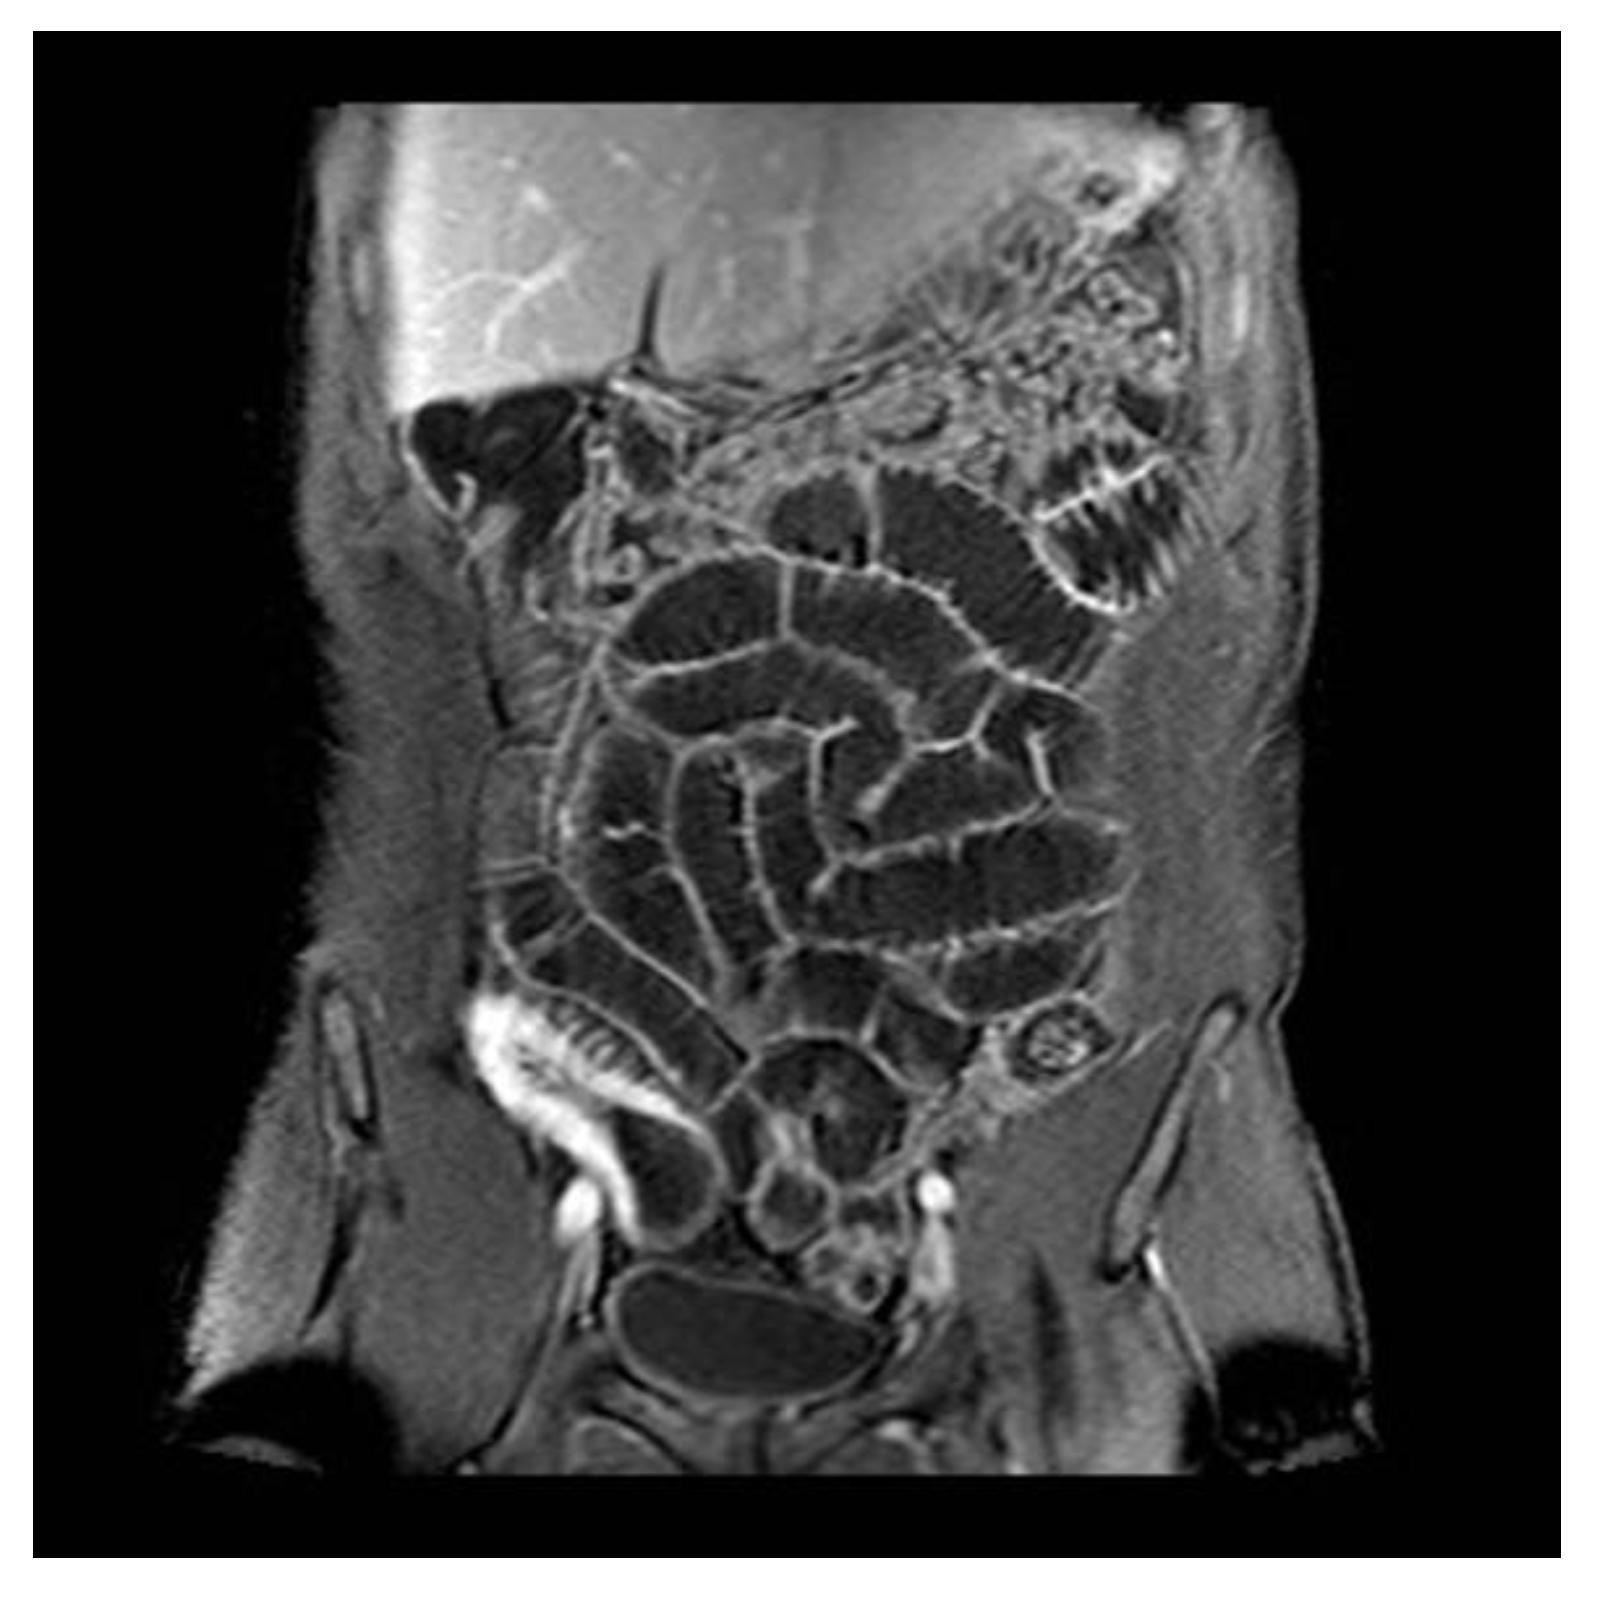

At our institution, high-resolution entero-MRI informed by a highly trained specialist is a very important tool used to differentiate between luminal affection only from patients who have a fibrotic stenosis (that could be an absolute indication for surgery). This is possible due to the ability of MRI to visualize the entire intestinal wall.

To sum up, the strongest indicators of inflammation are intramural edema, which is seen as hyperintensity on T2-weighted fat-saturated images. Other indicators are homogenous wall enhancement, mural thickness, mural ulcers, Comb sign (see Figure A2), and restricted diffusion on diffusion-weighted sequences.

Below there is an image of an ileocecal CD patient, showing a coronal contrast enhanced T1-weighted MR enteroclysis with biphasic oral contrast. This shows bowel wall thickening, hypervascularity, and Comb sign (engorgement of the mesenteric vessels with vascular dilatation, tortuosity with spacing of the vasa recta), indicating inflammation/luminal CD.

Figure A2.

MRI visualization of a patient with luminal affection (Comb sign).